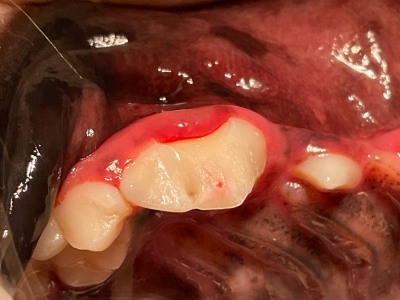

歯肉縁下(歯肉の中)まで破折し、神経も露出しています。

ラバーダムを装着し、歯髄保護を実施します。